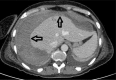

Endoscopic retrograde cholangiopancreatography (ERCP) is one of the most frequently performed procedures for the diagnosis and treatment of biliary-pancreatic diseases. ERCP-related complications total around 2.5% to 8%, with a mortality rate ranging from 0.5% to 1%. An exceptional ERCP complication is subcapsular hepatic hematoma, and few cases are reported worldwide.We present the case of a 52-year-old woman with a history of recurring upper abdominal pain and a clinical and ultrasonographic diagnosis of obstructive jaundice due to common bile duct stones. After 2 difficult endoscopic biliary procedures, common bile duct stones clearance was obtained. Post-ERCP course was symptomatic with upper abdominal pain and anemization with hemodynamic instability.CT scan demonstrated a 15 cm × 11 cm subcapsular hepatic hematoma filled with air and liquid on the surface of the right hepatic lobe. The patient was successfully treated with the embolization of a small branch of right hepatic artery angiographically identified as the cause of bleeding.Subcapsular hepatic hematoma after ERCP is a rare complication that must be taken into account in the differential diagnosis of symptomatic cases after ERCP. Its diagnosis is based on clinical and laboratory data and especially on imaging (ultrasound, CT, or MRI). Treatment is often conservative but, in some cases, embolization or percutaneous drainage or surgery may be necessary.